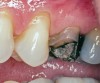

Replacement of existing restorations is responsible for 75% of all operative dentistry.15,19 The reasons for placement and replacement of restorations of direct restorative materials include: primary caries (Figure 1 and Figure 2); recurrent caries (Figure 3); poor margins (Figure 4 and Figure 5); restoration fracture (Figure 6 and Figure 7); tooth fracture (Figure 8); esthetics (Figure 9); non-carious tooth structure lost (attrition, abrasion, abfraction, erosion) (Figure 10); and pain/sensitivity.

Fig. 4 Defective margins. Mandibular first molar with an amalgam restoration with defective margins.

Figure 4  Defective margins. Mandibular first molar with an amalgam restoration with defective margins.

Figure 4